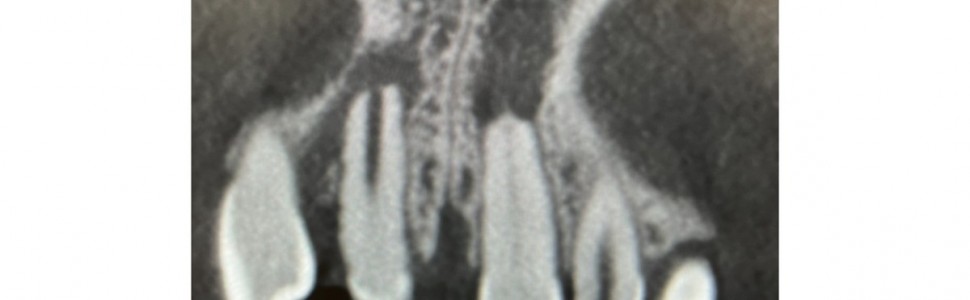

Leczenie powikłań po zwichnięciu całkowitym i replantacji zębów 11 i 21 u pacjentki młodocianej. Obserwacja 3-letnia

W pracy przedstawiono krok po kroku opis leczenia powikłań po zwichnięciu całkowitym zębów i ich replantacji u 9-letniej pacjentki. Zmiany zapalne okołowierzchołkowe i resorpcja zewnętrzna zostały wykryte przypadkowo, przed planowanym leczeniem ortodontycznym. Wykonano leczenie endodontyczne, zamknięto szerokie wierzchołki zębów 11 i 21 z użyciem MTA. Obserwacja 3-letnia potwierdziła sukces terapeutyczny.

The article presents a step-by-step description of the treatment of complications following complete tooth luxation and their replantation in a 9-year-old patient. Periapical inflammatory changes and external resorption were detected accidentally, before planning orthodontic treatment. Endodontic treatment was performed and the wide apices of teeth 11 and 21 were closed using MTA. A 3-year follow-up confirmed therapeutic success.